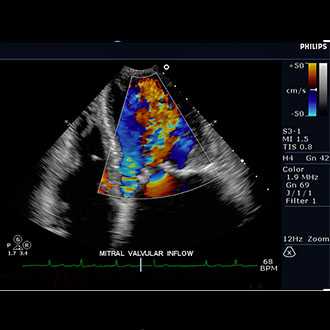

Doppler ultrasound is a special ultrasound technique that evaluates blood as it flows through a blood vessel, including the body's major arteries and veins in the abdomen, arms, legs and neck.

A Doppler ultrasound is a test that uses high-frequency sound waves to measure the amount of blood flow through your arteries and veins, usually those that supply blood to your arms and legs. ... The test provides your doctor with important information about the flow of blood through your major arteries and veins

In an ultrasound examination, a transducer both sends the sound waves into the body and receives the echoing waves. ... Doppler ultrasound, a special application of ultrasound, measures the direction and speed of blood cells as they move through vessels.